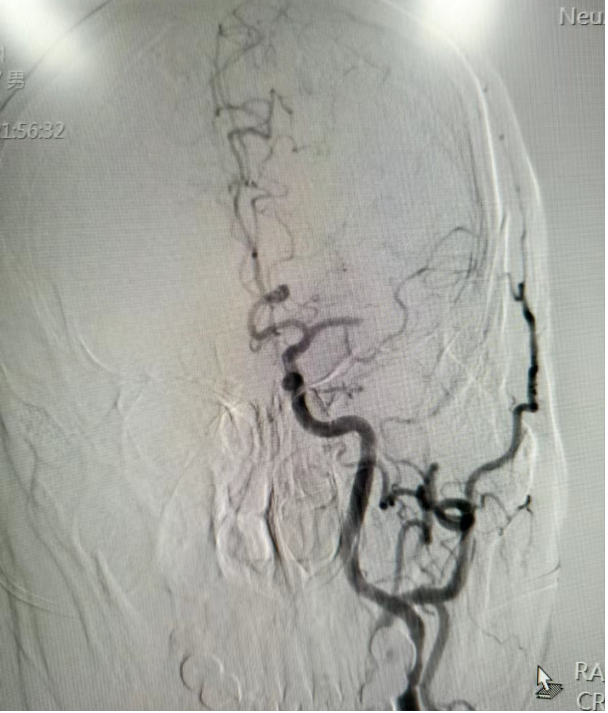

术前影像

术后开通影像

术中予左侧大脑中动脉Solitaire支架取栓+中间导管负压抽吸成功取出血栓,恢复血管再通。

术后1周患者肢体恢复良好,NIHSS评分2分,mRS评分1分。